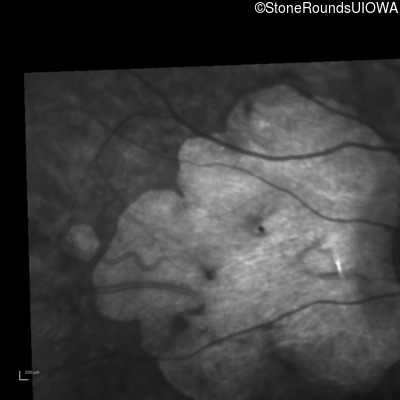

Infrared Fundus Photograph - Left - 20/500

Exemplar